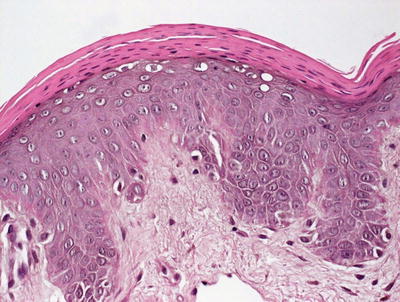

Histologic changes in acrodermatitis enteropathica include confluent parakeratosis, psoriasiform epidermal hyperplasia, marked diminution or total loss of the granular layer, marked spongiosis, and pronounced epidermal pallor limited to the upper one-half to one-third of the epidermis [3–5] (Figs. 15.3 and 15.4). Ballooning degeneration of the keratinocytes contributes to the pale staining within the epidermis. There are neutrophilic abscesses within the stratum corneum and upper portions of the epidermis. Within the dermis, the most common findings are a superficial perivascular, predominantly lymphoid infiltrate, occasionally with scattered eosinophils or neutrophils. Focal acantholysis has been described in lesions of acrodermatitis enteropathica [6]. Bullous variants and the presence of interface dermatitis have also been reported [7].

Fig. 15.3

Histologic findings in acrodermatitis enteropathica include pallor of keratinocytes in the upper portion of the epidermis, sometimes resulting in superficial blister formation. Minimal dermal inflammation is seen in most cases

Fig. 15.4

Thick parakeratosis overlies pale staining epidermis with focal hypogranulosis in acrodermatitis enteropathica